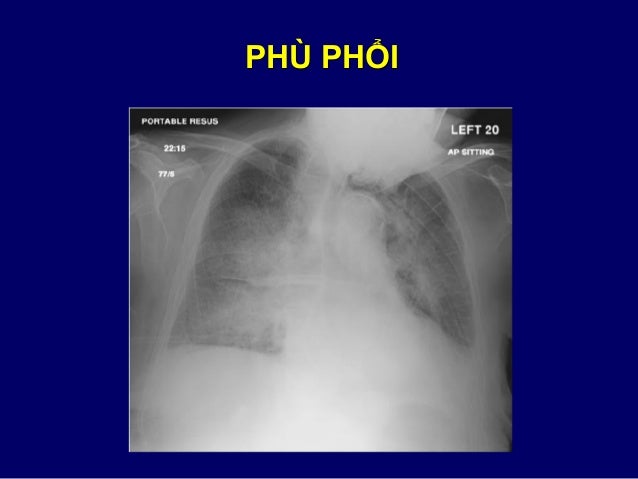

39. 39. LIỀM HƠI  Tập hợp khí thành dạng liềm ngăn cách thành hang với khối mờ bên trong  Thường xem là đặc hiệu cho Aspergillus trên hang có sẵn từ trước hoặc là do sự co kéo của vùng phổi hoại tử  Cũng có thể gặp trong các bệnh khác: lao, tăng sinh u hạt Wegener, xuất huyết trong hang, K phế quản

62. 62. PHÙ PHỔI